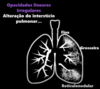

O que são as reticulções ?

Opacidades lineares e irregulares do pulmão, decorrente de alterações do interstício pulmonar

Quais os tipos de reticulções ?

Linear

Grosseiras

Reticulonodular

Como diferenciar consolidações de reticulações ?

Na Reticulação o vaso é visível ao passar por meio da área alterada, enquanto na consolidação não é visível devido ao sinal da silhueta